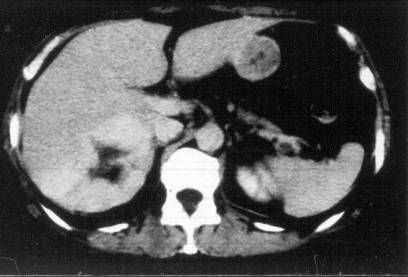

HCC appears mostly as low density on the native CT scan, with inhomogeneous structure and a sorrounding with a slightly increased density bearing capsule can be also detected. The completion of the three-phase CT scan (arterial, venous, late) is especially important in case of a suspicion of HCC. The appearance of the inhomogeneous lesion in the arterial phase, including sometimes non contrast enhancing necrotic areas inside, bears with a diagnostic value. The capsule can be detected best in the venous phase.

Concerning the HCC, the knowledge of history is very important for the decision and usually the oncoteams consider the performance of an imaging modality guided biopsy basically important for the further therapeutic decisions (because of the hystological validation rather core biopsy should be performed! (Figure 26, 27, 28).

Figure 26: HCC, verified with FNAB, US

Figure 27: HCC, TAE, agniography

Figure 28: HCC, native CT after TAE